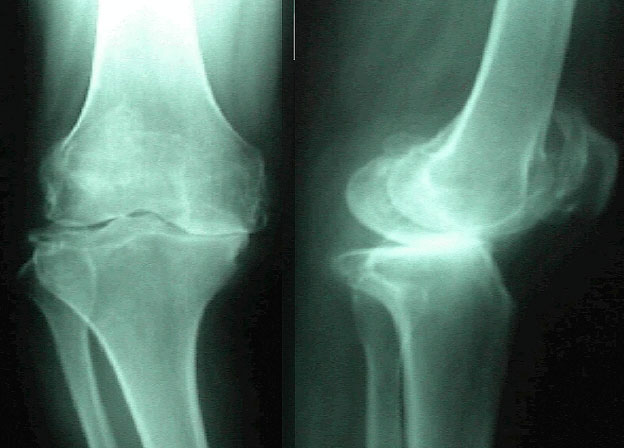

減慢腰及膝蓋關節退化

年齡的增長,加上日積月累的操勞工作,退化的問題就像呼吸一樣來得自然,勞損愈多,關節退化就愈快。想要減慢腰部和膝蓋關節退化的速度,可做的事情有很多,其中之一,就是要養成隨時保持正確姿勢的習慣,然後要記住如何維持不讓關節過度受壓的姿勢。

從年輕時就有壞習慣的人,隨著組織老化帶來肌力衰退所造成支撐力的下降,會讓保持正確姿勢變得相當困難。如不加以處理,姿勢的問題就會愈來愈嚴重,而導致無法平均分散關節承受的壓力,就會成為腰及膝蓋關節疼痛的來源。如果你是愛惜自身關節的人,現在就應該重新開始進行正確姿勢的訓練。